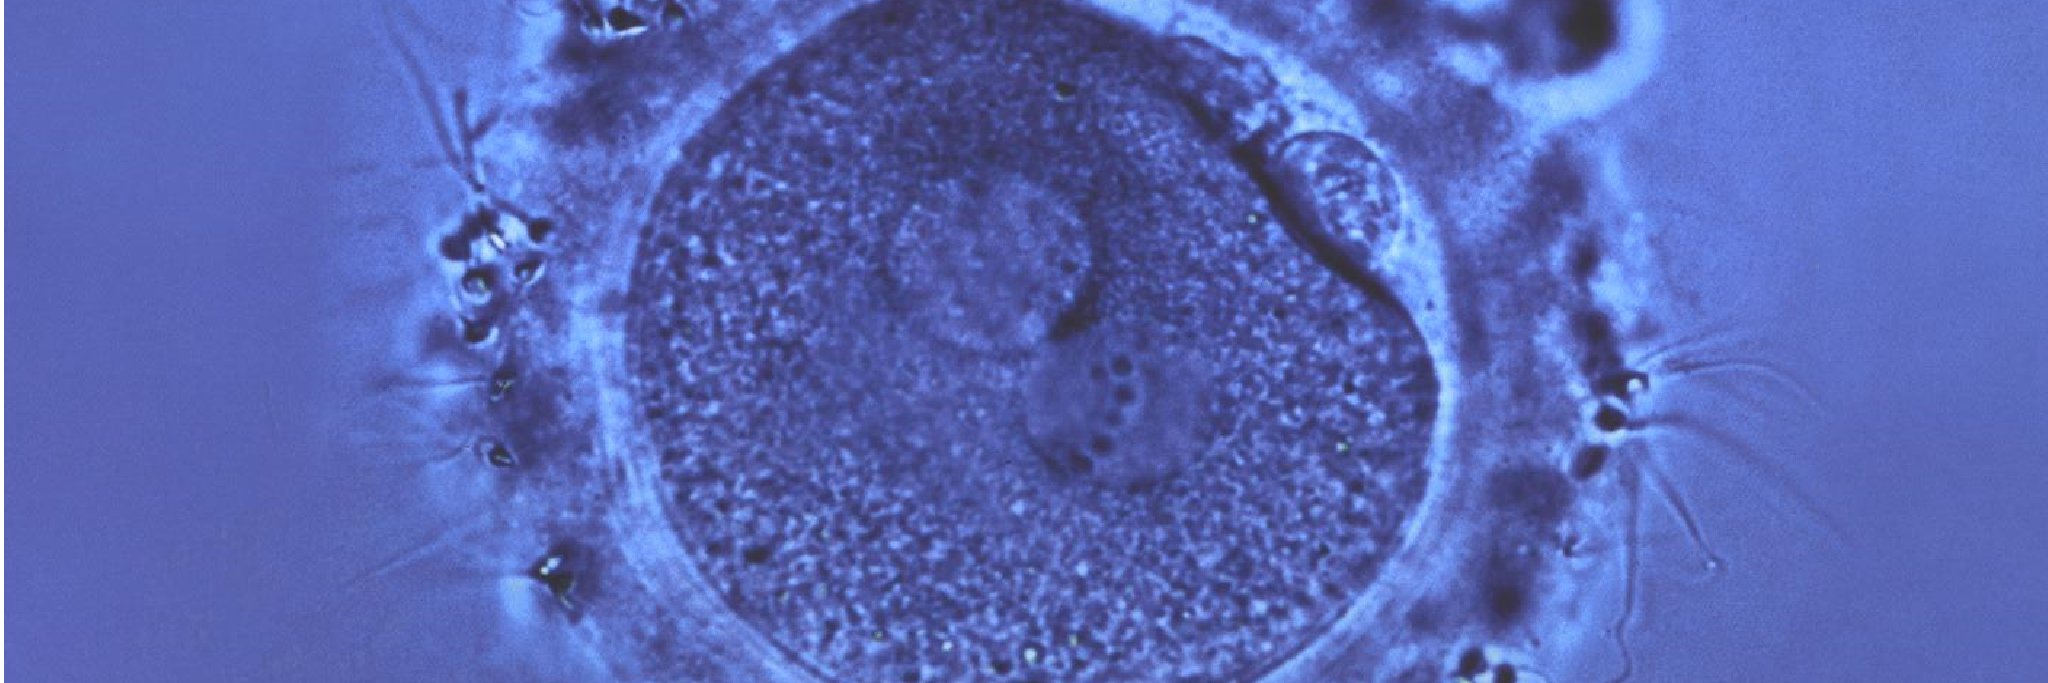

Factors to consider for fertility surgery with endometriosis contemporaryobgyn.net/view/factors-t…